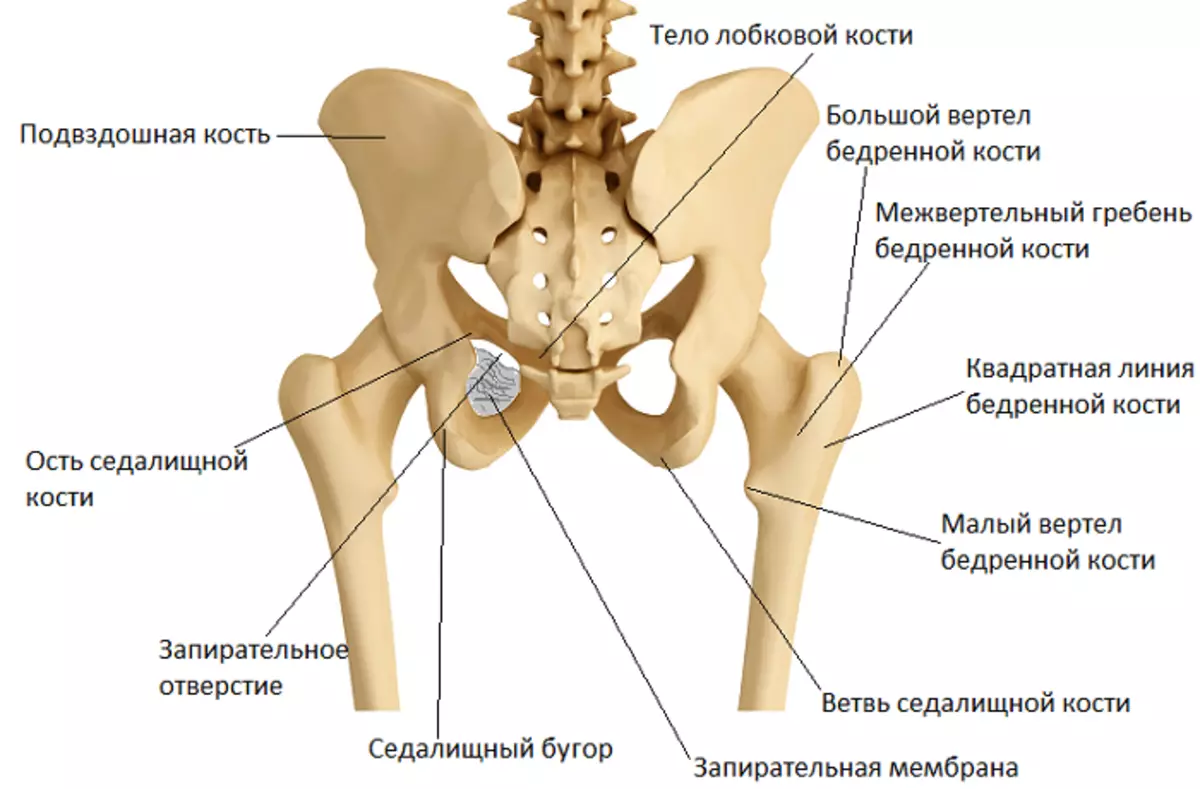

Структура позвоночника: сегменты и тазовые отделы в фотографиях